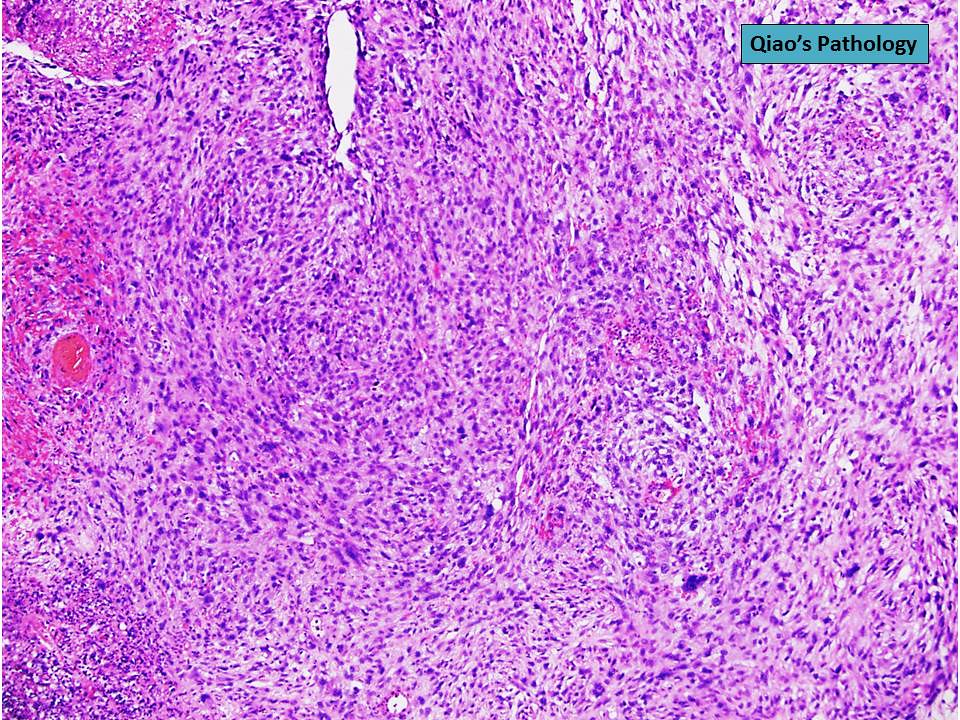

Spindle Cell Hepatocellular Carcinoma . Morphologically, conventional hcc show 4 major architectural growth patterns: Trabecular, solid, pseudoglandular/acinar, and macrotrabecular. Spindle cell hepatocellular carcinoma (sphcc) has rarely been reported, and its clinicopathologic characteristics, histogenesis, and prognosis after hepatic resection have yet to be. It has been reported that hepatocellular carcinoma (hcc) with spindle cell tumor accounts for 1.8% of all hccs, but spindle cell tumors that do not show an. Most common (> 80%) primary liver. Primary malignancy of liver with hepatocellular differentiation.

Qiao's Pathology (Spindle Cell) Carcinoma of … Flickr Spindle Cell Hepatocellular Carcinoma Most common (> 80%) primary liver. It has been reported that hepatocellular carcinoma (hcc) with spindle cell tumor accounts for 1.8% of all hccs, but spindle cell tumors that do not show an. Primary malignancy of liver with hepatocellular differentiation. Trabecular, solid, pseudoglandular/acinar, and macrotrabecular. Spindle cell hepatocellular carcinoma (sphcc) has rarely been reported, and its clinicopathologic characteristics, histogenesis, and. Spindle Cell Hepatocellular Carcinoma.